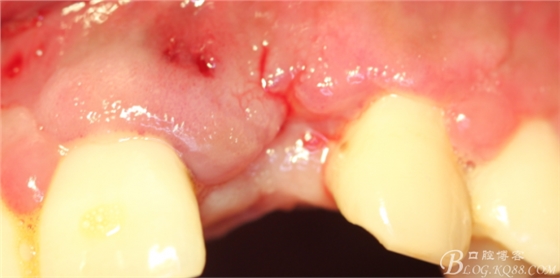

4個(gè)月后,唇側(cè)豐滿度尚可,與鄰牙之間齦乳頭完整。

保留齦乳頭翻小瓣。

翻開后驚喜的發(fā)現(xiàn),術(shù)區(qū)成骨非常好,去除部分骨才暴露那顆長(zhǎng)鈦釘。